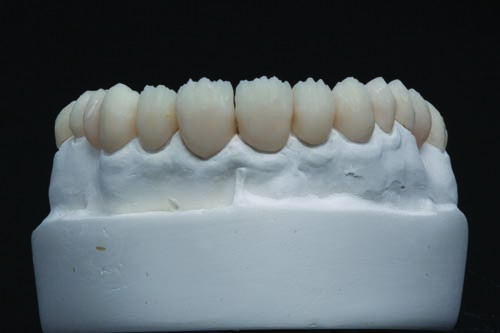

Figs. 23 and 24: After milling, the Telio CAD provisional was seated back onto the model to confirm fit and form from the labial and lingual aspects.

Fig. 28: The completed Telio CAD provisional restorations were tried back onto the model to verify fit and aesthetic qualities.